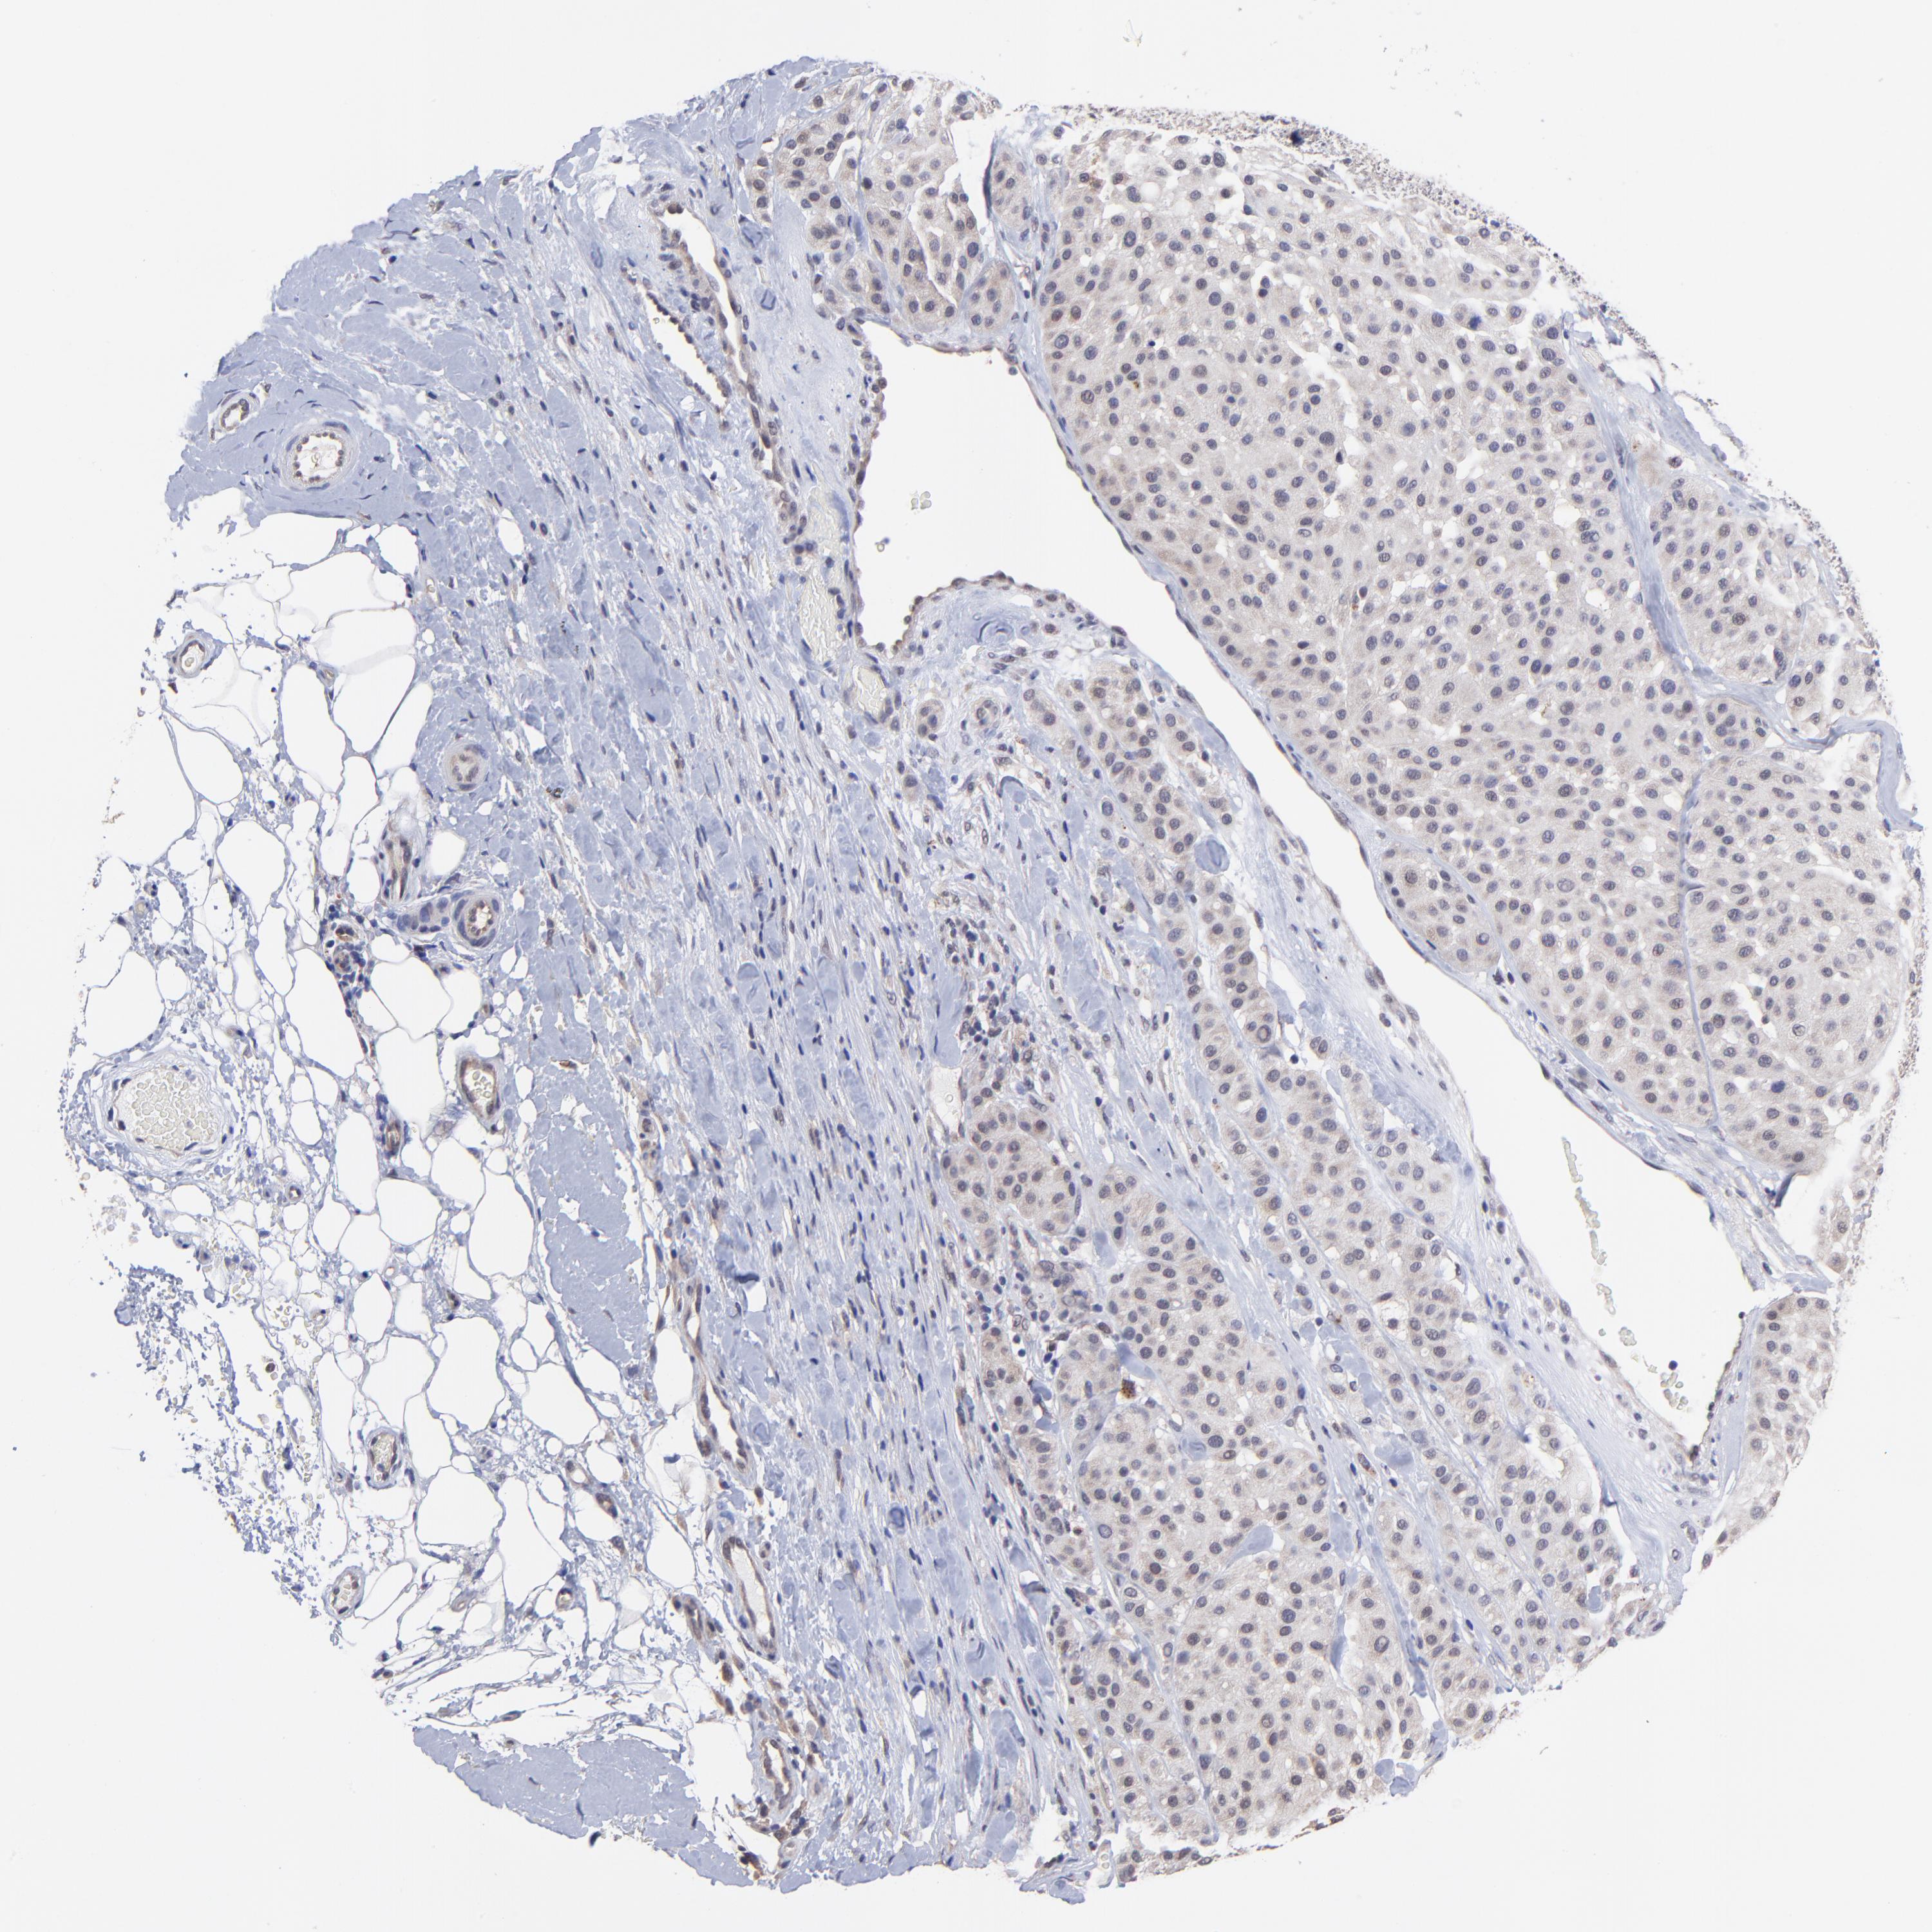

MELANOMA - Protein expressioni

A mouse-over function shows sample information and annotation data. Click on an image to view it in a full screen mode. Samples can be filtered based on level of antibody staining by selecting one or several of the following categories: high, medium, low and not detected. The assay and annotation is described here.

Note that samples used for immunohistochemistry by the Human Protein Atlas do not correspond to samples in the TCGA dataset.

Antibody stainingi

Antibody staining in the annotated cell types in the current human tissue is reported as not detected, low, medium, or high, based on conventional immunohistochemistry profiling in selected tissues. This score is based on the combination of the staining intensity and fraction of stained cells.

Each image is clickable and will lead to virtual microscopy that enables deeper exploration of all samples and also displays staining intensity scores, fraction scores and subcellular localization as well as patient and tissue information for each sample.

Antibody HPA003203

Staining

High

Medium

Low

Not detected

Intensity

Strong

Moderate

Weak

Negative

Quantity

>75%

75%-25%

<25%

None

Location

Nuclear

Cytoplasmic/membranous

Cytoplasmic/membranous,nuclear

Malignant melanoma, NOS

Malignant melanoma, Metastatic site